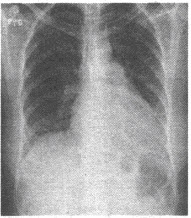

�У�28�꣬���2���£��е�������Ƭ��ͼ

�У�28�꣬���2���£��е�������Ƭ��ͼ

�У�28�꣬���2���£��е�������Ƭ��ͼ